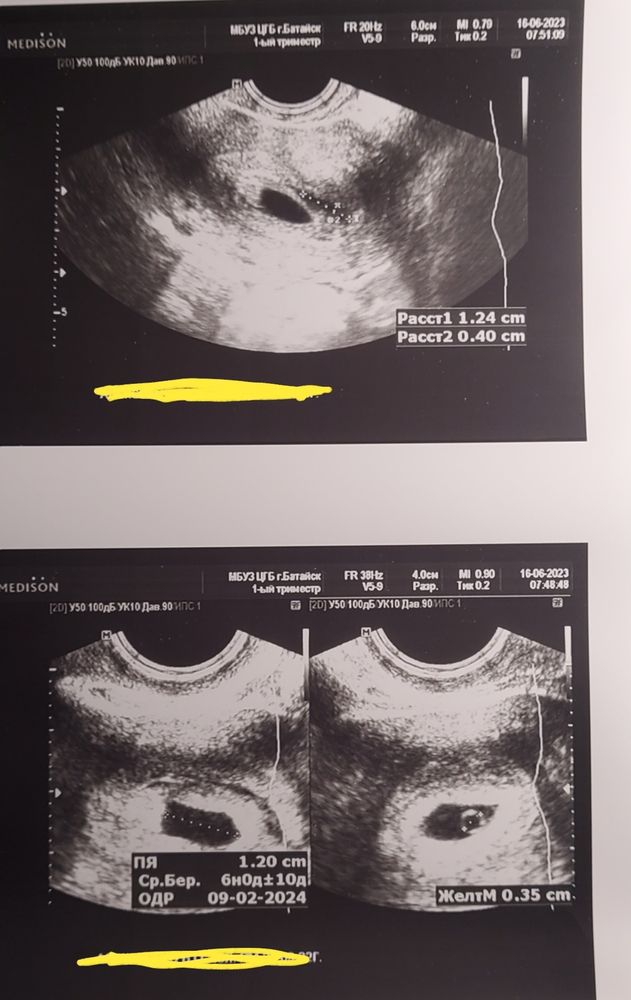

Сделали Узи в больнице, плодное яйцо в полости, образовался желточный мешочек. Не поняла, вилит она эмбрион или нет. Говорит рано.

Отслойка 12 мм на 4 мм. Плодное яйцо тоже 12 мм